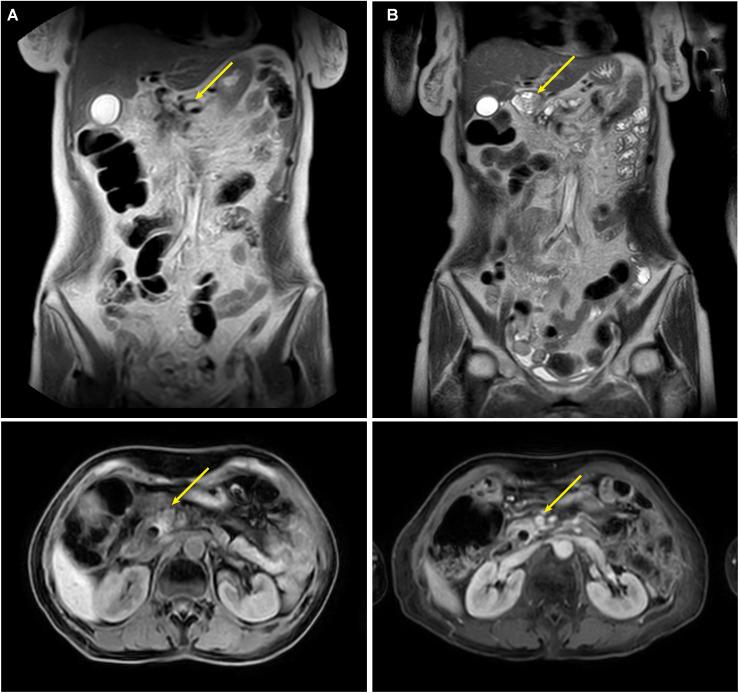

Malignant obstructive jaundice (MOJ) due to tumor compression or invasion of the bile duct carries a grave prognosis. We report a case of a 54-year-old female patient (height: 160 cm, weight: 55 kg, BMI: 21.5 kg/m², ECOG performance status: 1, with type 2 diabetes mellitus) advanced pancreatic head cancer causing MOJ, managed with a multidisciplinary approach. Initial endoscopic retrograde cholangiopancreatography (ERCP) with an 8.5 Fr plastic stent failed due to occlusion after 20 days, leading to bilirubin rebound. Emergency percutaneous transhepatic cholangial drainage (PTCD) followed by biliary metal stent (8 mm × 80 mm) and iodine-125 seed implantation effectively relieved obstruction, reducing total bilirubin (TBIL) from 116.9 to 45.6 μmol/L within seven days. Subsequent tomotherapy (TOMO, 66 Gy to gross tumor volume) and a personalized regimen of S1 (tegafur, 20 mg/day), nimotuzumab, and pembrolizumab, following intolerance to gemcitabine + nab-paclitaxel (AG), achieved a 78% reduction in CA19-9 and sustained biliary patency. At one-year follow-up, TBIL was 18.2 μmol/L, direct bilirubin (DBIL) was 9.8 μmol/L, and the patient reported a good quality of life (Karnofsky score: 90). This case demonstrates the efficacy of sequential PTCD, seed stent, and targeted-immunotherapy, offering a practical model for managing advanced pancreatic cancer with MOJ.

因肿瘤压迫或侵犯胆管导致的恶性梗阻性黄疸(MOJ)预后严重。我们报告一例54岁女性患者(身高:160 cm,体重:55 kg,BMI:21.5 kg/m²,东部肿瘤协作组体能状态:1,患有2型糖尿病),其晚期胰头癌导致MOJ,采用多学科方法进行治疗。最初的内镜逆行胰胆管造影(ERCP)置入8.5 Fr塑料支架,20天后因堵塞失败,导致胆红素反弹。紧急经皮经肝胆管引流(PTCD),随后置入胆道金属支架(8 mm×80 mm)并植入碘-125粒子,有效缓解了梗阻,7天内总胆红素(TBIL)从116.9降至45.6 μmol/L。随后进行断层放疗(TOMO,肿瘤总体积给予66 Gy),以及在患者对吉西他滨+纳米白蛋白结合型紫杉醇(AG)不耐受后采用的S1(替加氟,20 mg/天)、尼妥珠单抗和帕博利珠单抗个体化方案,使CA19-9降低了78%,并维持了胆道通畅。在一年的随访中,TBIL为18.2 μmol/L,直接胆红素(DBIL)为9.8 μmol/L,患者报告生活质量良好(卡诺夫斯基评分:90)。该病例证明了序贯PTCD、粒子支架和靶向免疫治疗的疗效,为晚期胰腺癌合并MOJ的管理提供了一个实用模型。